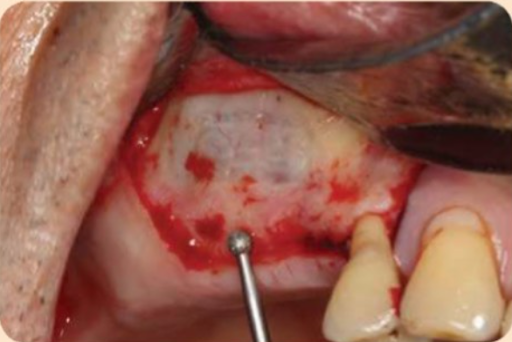

- Thiết kế cửa sổ xương đi theo đường viền của xoang hàm và các cấu trúc giải phẫu lân cận. Thông thường, có hai kỹ thuật để tạo cửa sổ: “kỹ thuật của sập” và “kỹ thuật cửa mở”. Trong kỹ thuật của sập, cửa sổ xương được nâng vào bên trong khoảng trống sau nâng xoang. Dụng cụ quay như mũi khoan carbide hoặc kim cương tròn được sử dụng dưới nước bơm rửa (Hình dưới đây), và cửa sổ xương có thể được nâng và để lại bên trong khoảng trống sau nâng xoang. Ngược lại, trong kỹ thuật cửa mở, cửa sổ xương sẽ được lấy đi bằng cách mài mỏng xương. Trong quá trình phẫu thuật, có thể quan sát thấy màng Schneiderian màu xanh.